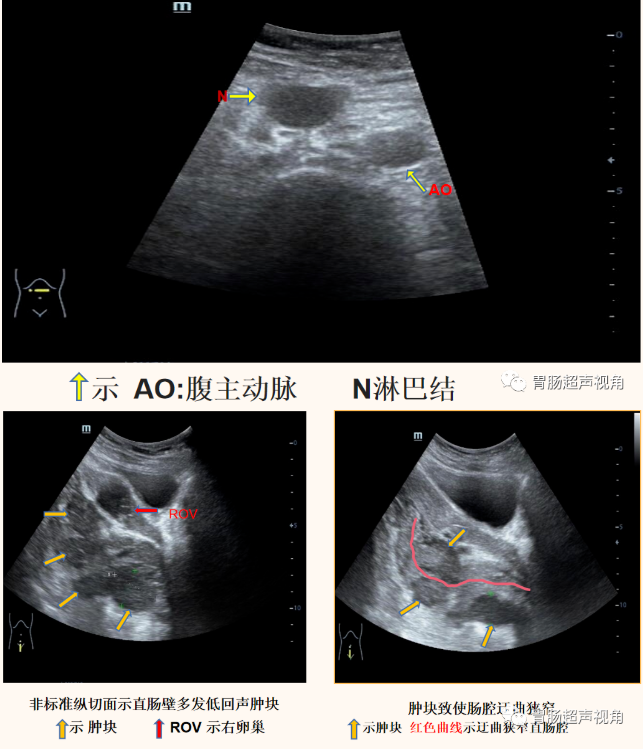

超声检查(2022-01-11日):

• 腹膜后(脐上方)腹主动脉前方可见一淋巴结,大小约2.0x1.4x1.9cm,呈低回声,CDFI:其内未见明显血流信号。

• 直肠灌入300ml造影剂经腹探查:直肠肠腔重度狭窄,仅见液体呈线状迂曲缓慢进入。

• 直肠肠壁可见多发低回声结节向腔内隆起,较大着位于直肠后壁,大小约5.2x3.3x2.0cm(长x宽x厚),前壁另可见片状不规则增厚,较厚处约1.1cm,累及长度约4.0cm(环绕肠壁约1/2周),肠粘膜面可见一较大凹陷,长约2.2cm,深约0.7cm,粘膜凹陷处可见强回声附着。

• 逆行经肛门灌入造影剂,直肠腔明显狭窄,造影剂迂曲缓慢进入直肠腔